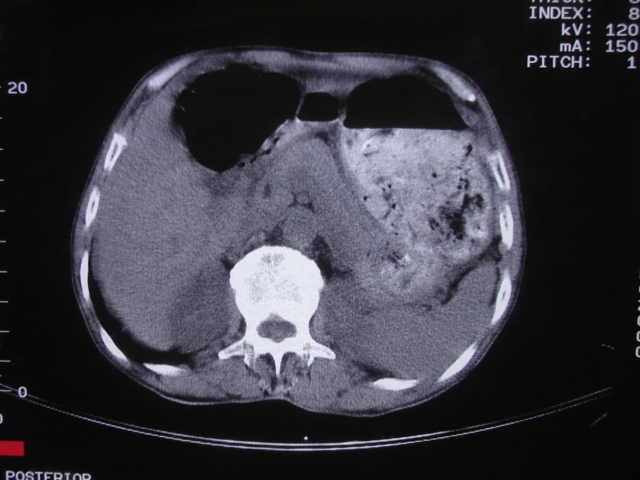

以下是引用深泽交通医院在2008-7-17 12:39:00的发言:[br]胃下垂;胃窦占位